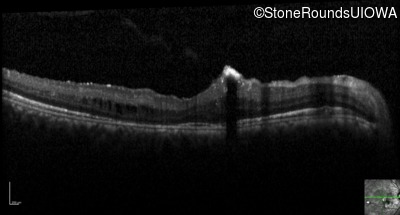

Optical Coherence Tomography - Right - 20/40 -1

Exemplar / OCT Stack

OCT Stack

Optical Coherence Tomography - Left - 20/20 -2